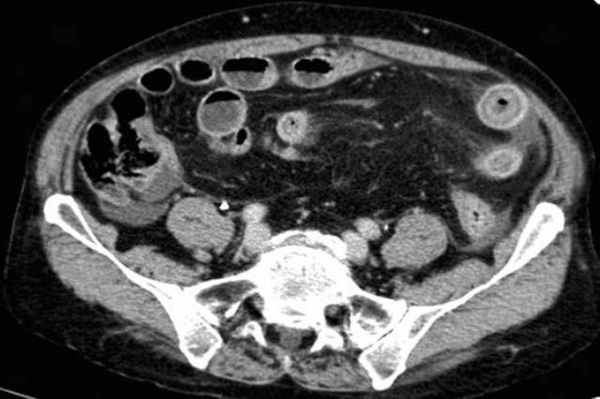

-свободная жидкость между расширенными петлями кишечника, зачастую в виде пикантной детали женского туалета-трусиков танга, поэтому в многих источниках описывается как признак "танга" (tanga sign);

-свободная жидкость в брыжеечных карманах;

-свободная жидкость в брюшной полости.

Примеры скопления жидкости между петлями кишечника (танга) и в карманах брыжейки при декомпенсированной форме.